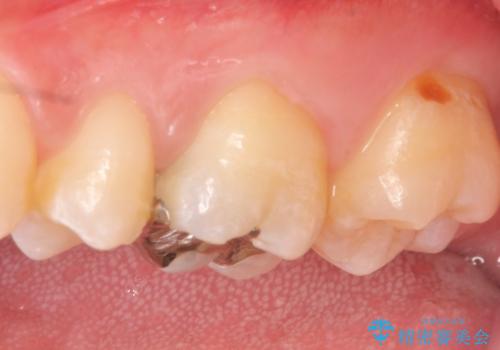

- 3日ほど前から何もしなくても左上奥歯がズキズキ痛むので診て欲しいといらっしゃった方の症例です。

検査の結果左上6に持続痛を認めたため根管治療を行い、症状の緩解を確認後オールセラミッククラウンによる補綴を行いました。